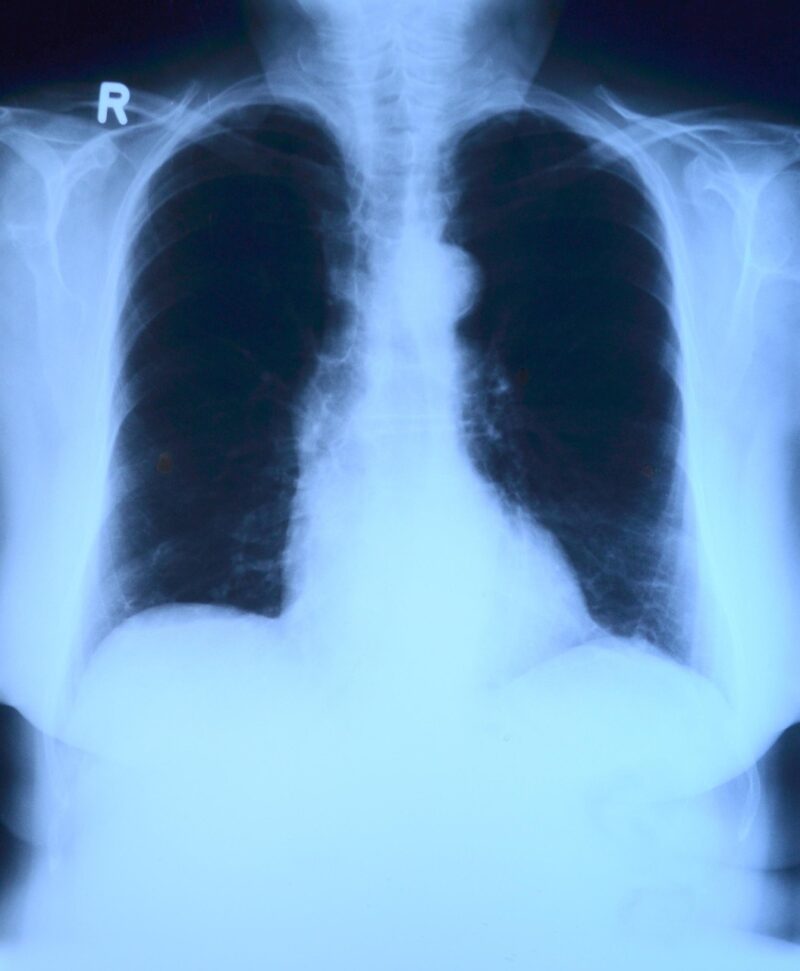

Un equipo de investigación de la Universidad de Cádiz ha creado un sistema basado en aprendizaje profundo que localiza y clasifica automáticamente anomalías en radiografías de tórax. Los resultados mejoran la precisión de otros métodos y lo validan como una herramienta con potencial para dar soporte a la evaluación precoz de patologías del pulmón.

De esta manera, el sistema, denominado Mamba-YOLOvX, se presenta como un aliado rápido y preciso para neumólogos y radiólogos en el diagnóstico de enfermedades pulmonares. En un artículo, publicado en la revista Expert Systems with Applications, los expertos lo presentan y demuestran que la localización de lesiones de diversos tamaños es más rápida y efectiva que con otras herramientas. “En muchas ocasiones, algunas lesiones pulmonares pueden pasar desapercibidas en los exámenes radiológicos, dada la gran dificultad en la interpretación de esta modalidad de imagen médica. Incluso, cuando la enfermedad pasa de un estado inicial a otro de mayor gravedad, la evaluación por parte del experto está sujeta, a menudo, a cierta subjetividad y variabilidad”, indica a la Fundación Descubre el investigador de la Universidad de Cádiz, Daniel Sánchez Morillo, coautor del artículo.

Los expertos han entrenado a la IA con miles de radiografías diferentes y han logrado una mejora en la precisión de diagnóstico con respecto a otros métodos desarrollados recientemente. “Es especialmente efectivo en el caso de lesiones pequeñas. Por eso, este sistema tiene todo el potencial para ser aplicado como herramienta de apoyo clínico en la detección precoz de lesiones pulmonares”, añade el investigador.

El nuevo modelo combina la información global de la imagen, es decir, el contexto general, como la forma de los pulmones o la posición del corazón, con la información local, los pequeños detalles que pueden indicar lesiones o irregularidades. Esto permite detectar problemas a diferentes escalas.

Además, el sistema incorpora mecanismos de atención espacial y de canal, que funcionan como filtros inteligentes que se concentran sólo en las zonas relevantes de la radiografía y en las características más útiles, ignorando lo que no aporta información. Así, sólo atenderá al pulmón, apartando las costillas o los hombros, y discriminará zonas sanas para centrarse sólo en aquellas que puedan presentar alteraciones.

También incluye bloques de escaneo selectivo, que analizan la imagen en distintas resoluciones y permiten identificar lesiones muy pequeñas, que suelen pasar desapercibidas. Se podría decir que parte de la imagen completa, al mismo tiempo que amplía distintas zonas de la radiografía.